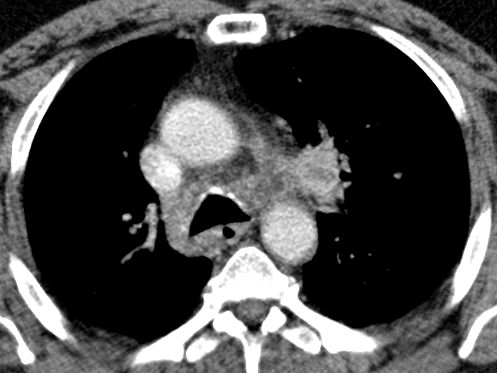

| Embolie | 55-jähriger Mann mit SCC rechts zentral mit

Verschluss der Mittellappens und Stenose des Zwischenbronchus T4 N2b Mo. Vom

Tumor eingeschlossen eine Pulmonalarterie mit einer kreisrunden Aussparung

durch einen Embolus.![]() | ||